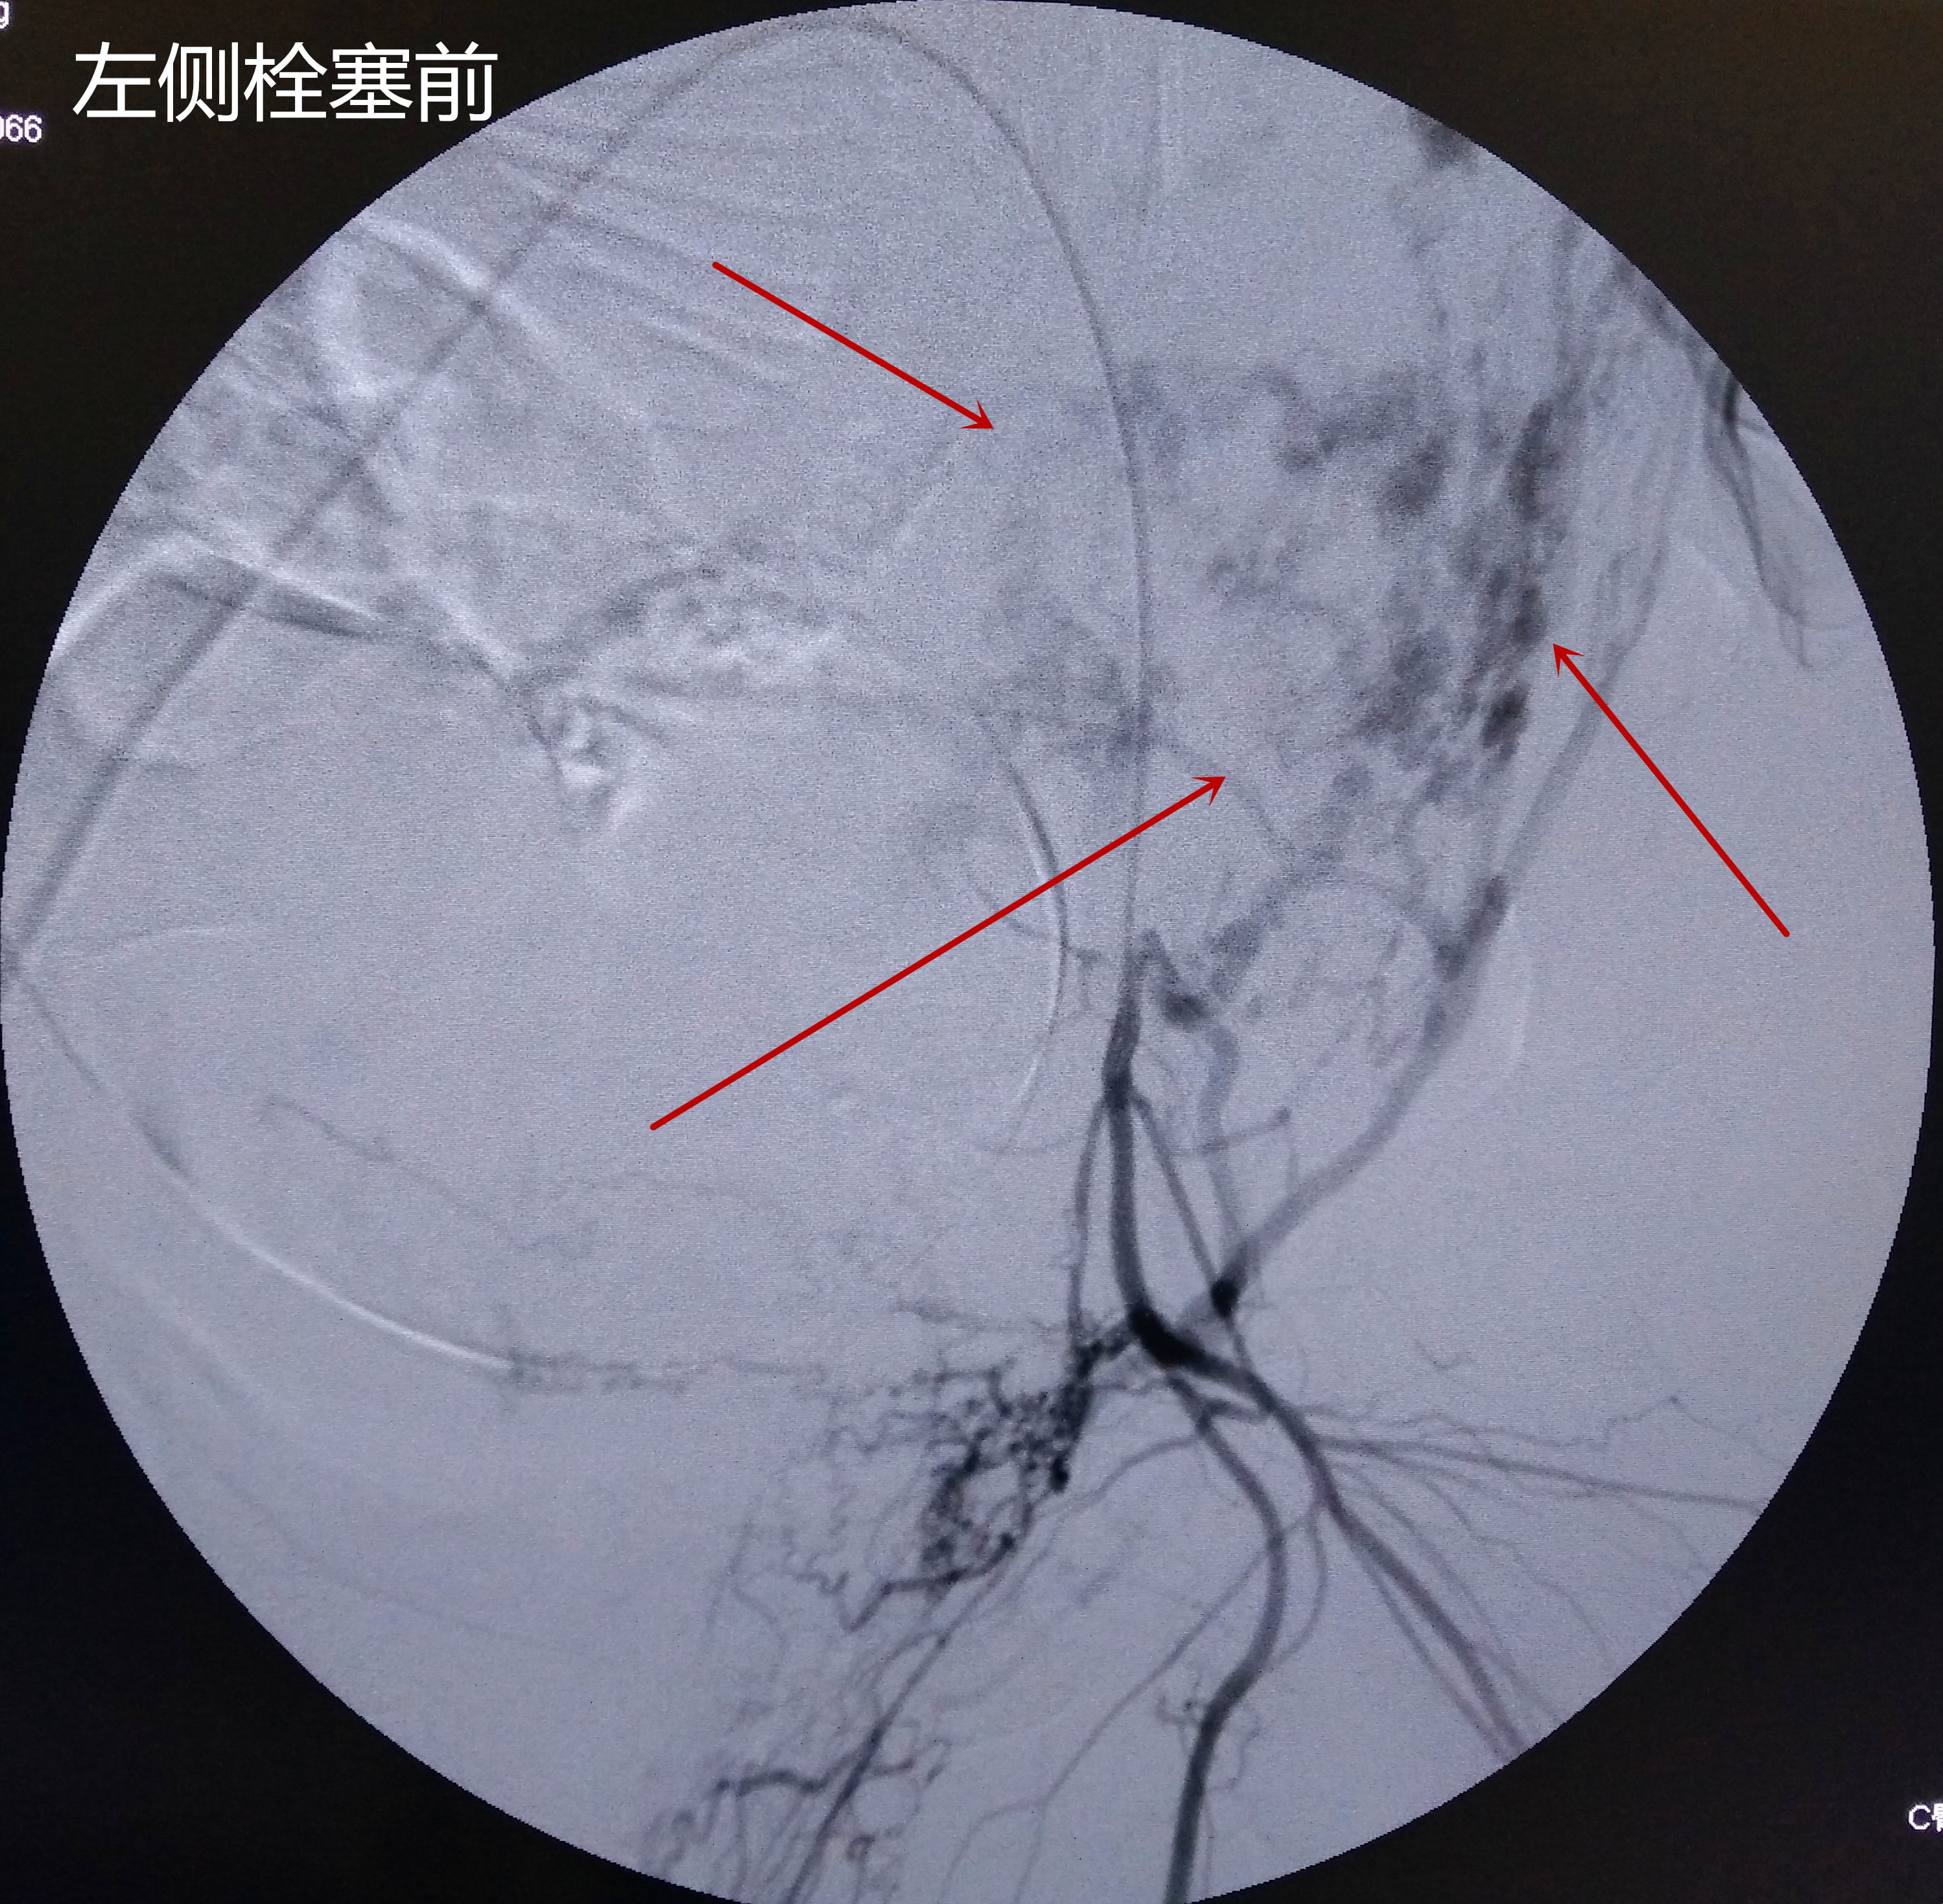

手术在数字减影血管造影机(DSA)引导下进行,手术由放射科唐小平主任、王琦、杨九炜医师操作,杜海云主管护师紧密配合。手术采用改良Seldinger技术穿刺右侧股动脉成功后,行左侧子宫动脉造影:左侧子宫动脉走行明显迂曲,管径明显增粗;遂将导管头端至于左侧子宫动脉中,经导管注入碘佛醇明胶海绵混悬剂经导管行子宫动脉栓塞术,栓塞完成后再次造影可见左侧子宫动脉主干以下不再显影。同法栓塞右侧子宫动脉成功后立即送入手术室行“子宫下段剖宫产术”。剖宫产术中出血约600ml,生命体征平稳,术后产妇安返产科病房,在产科医护人员的精心护理下,目前患者恢复良好,可下地活动。